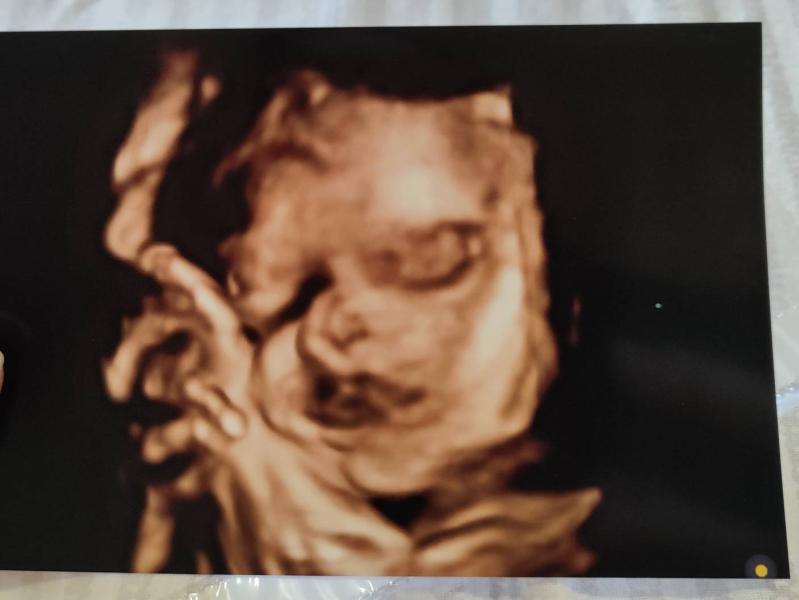

Наша красотка категорически отказалась показывать лицо на 3д узи. Кое-как врач сделала хотя-бы какое-то фото😅

Тут врач тоже очень старалась, она её всяко разно шебуршила, меня крутида с боку на бок. То, что такой снимок получился, при положении ребёнка - уже чудо😁

@alenka_mamochka_ я час была на узи🙈 но тоже да, почти все время в ч/б. Но врач очень детально все посмотрела и измерила, показала каждый орган, мне это понравилось) если бы не положение дочки, точно бы хороший снимок получился